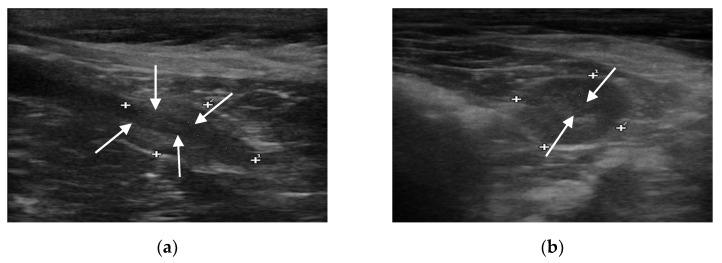

Prostatic neoplasia (PN) occurs in 5-7% of dogs with prostatic disease, with castrated dogs having the same or higher prevalence when compared to intact dogs. Considering the promising results achieved by performing contrast-enhanced ultrasound (CEUS) in intact dogs to detect PN, the present study aimed to acquire data on the prostatic perfusion pattern in neutered dogs. CEUS was performed in 64 neutered dogs, using a 5-7.5 MHz linear transducer with coded harmonic capability, dedicated analytical software, and a second-generation contrast agent, SonoVue. After B-mode evaluation was performed to assess mean prostate volume, the CEUS examination was undertaken. The flow of contrast agent was visible 10 s after injection. The subcapsular vessels were highlighted and produced rapid peripheral rim enhancement. Subsequently, the contrast agent reached the prostatic urethra via the parenchymal arterioles and gradually reached the entire prostate. Perfusion peak intensity (PPI) and time to peak (TTP) values were respectively 45.3% and 34.1 s. The measured parameters were compared with those obtained in previous studies on intact dogs with normal and with pathological patterns. In this study, CEUS showed features that may be promising for its use as a diagnostic tool for early detection of PN in neutered dogs.

前列腺肿瘤(PN)发生于5% - 7%患有前列腺疾病的犬类中,与未绝育的犬相比,绝育犬的患病率相同或更高。鉴于在未绝育犬中进行对比增强超声(CEUS)检测PN取得了有前景的结果,本研究旨在获取绝育犬前列腺灌注模式的数据。对64只绝育犬进行了CEUS检查,使用具有编码谐波功能的5 - 7.5 MHz线性换能器、专用分析软件和第二代造影剂声诺维。在进行B模式评估以评估平均前列腺体积后,进行了CEUS检查。注射造影剂10秒后可见造影剂流动。包膜下血管突出并产生快速的周边边缘增强。随后,造影剂通过实质小动脉到达前列腺尿道并逐渐到达整个前列腺。灌注峰值强度(PPI)和达峰时间(TTP)值分别为45.3%和34.1秒。将测量参数与先前关于具有正常和病理模式的未绝育犬的研究中获得的参数进行比较。在本研究中,CEUS显示出的特征可能使其有望作为早期检测绝育犬PN的诊断工具。